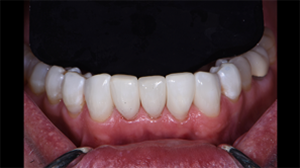

Fig. 7: Labial view of the completed case. Four black triangles closed between teeth #22-27.

Fig. 8: Lingual view of completed case to show the anatomic shapes and polish pleasing to the tongue.

Fig. 9: Immediate post-operative view with contrast. Note the immediate closure of spaces, atraumatic tissue condition and tissue adaptation to the new shapes.

Fig. 10: Retracted views. Teeth are still dehydrated, but color blending with Filtek Universal can already be appreciated.